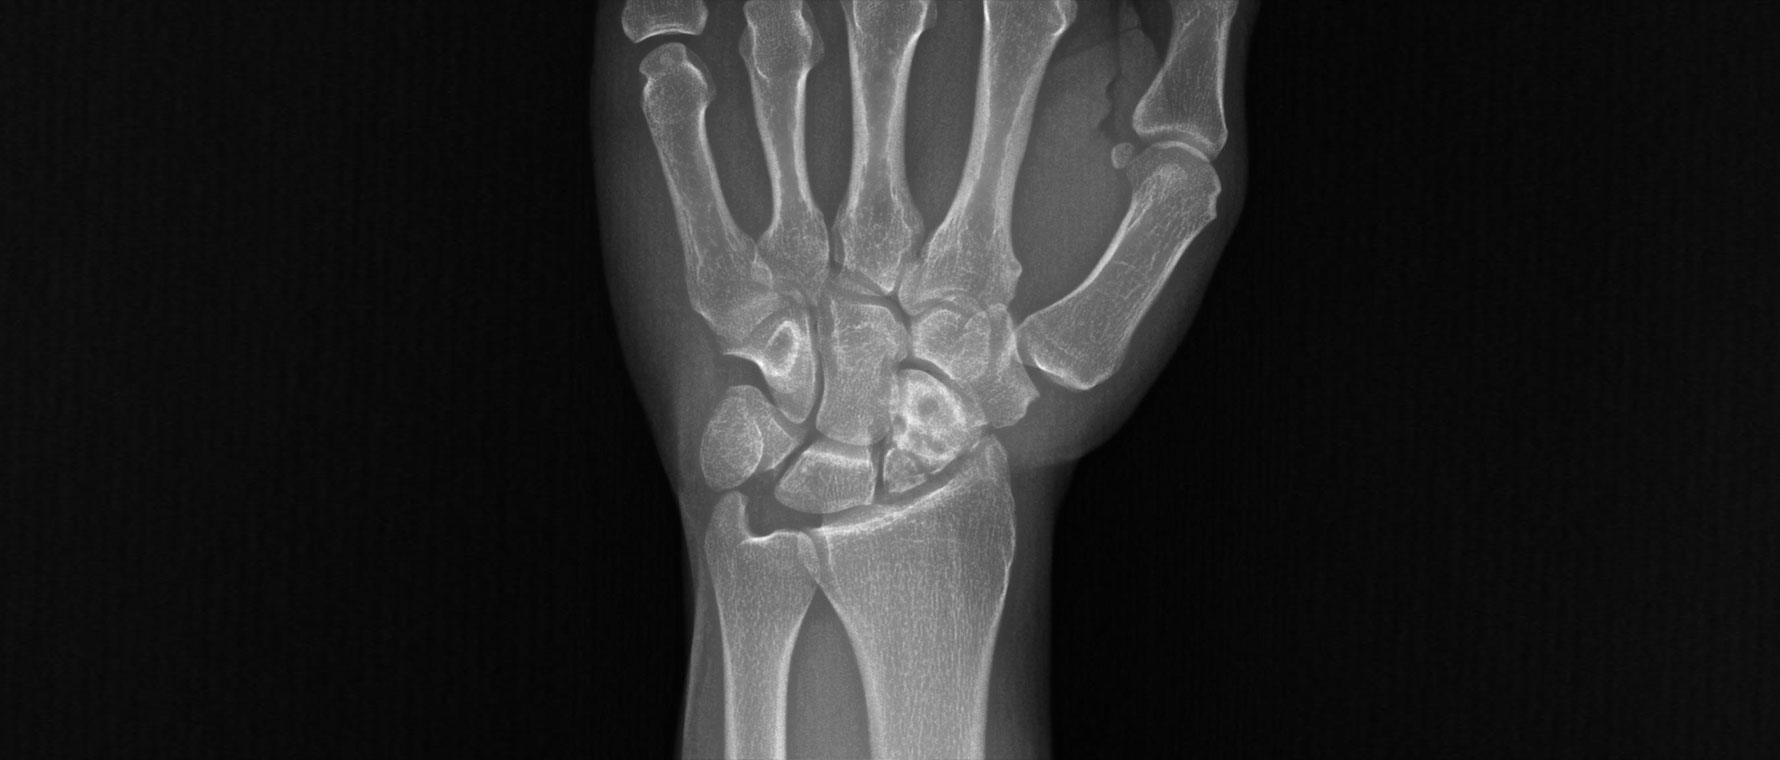

El Bileği Kireçlenmesi

El bileği kireçlenmesi, eklem kıkırdağının aşınması sonucu ağrı ve hareket kısıtlılığıyla seyreden bir hastalıktır. Travmalar, bağ yaralanmaları ve eski kırıklar en sık nedenlerdir. Hastalar bilekte sertlik, şişlik ve güç kaybı tarif eder. Tanı muayene ve görüntüleme ile konur. Tedavide ağrı kesiciler, atel ve fizik tedavi uygulanabilir. El bileği kireçlenmesi ağırlaşmamış hastalarda kısmi olarak el bileği dondurularak hem ağrı hafifletilir hem de el bileği hareketleri kısmi olarak korunur. Buna karşın ilerlemiş hastalarda tüm el bileğinin dondurulması ameliyatı yapılır.